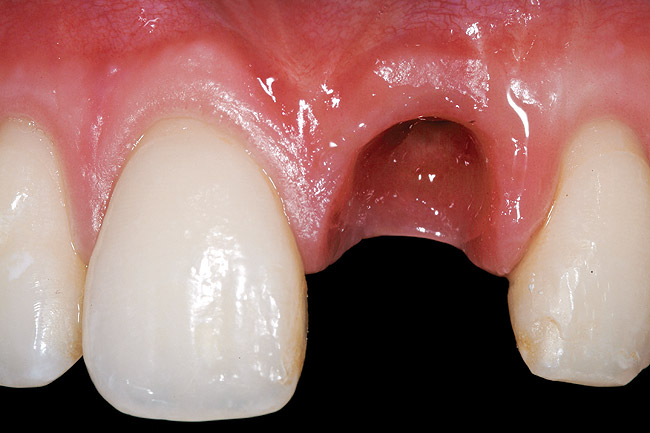

A 24-year-old non-smoking man presented for treatment of a horizontally fractured left central incisor (Figure 21 and Figure 22). The patient requested to have an implant placed to replace the left central incisor as to not have any damage to the adjacent dentition.

Complicating the treatment site was the apically positioned facial height of contour at the left central incisor, and the adjacent left lateral incisor (Figure 21.) Additional sites of recession were present throughout the oral cavity and were to be addressed by the tunnel grafting procedure previously outlined.

The patient opted for the third option. After administration of an appropriate local anesthetic, a frenectomy was performed using a Nd:Yag laser. This would allow for the loosening of the facial tissues and the coronal repositioning of the pouch at the termination of the procedure. After the frenectomy, the left central incisor was removed by an atraumatic technique preserving the soft tissue emergence profile (Figure 23). Debridement of the extraction socket preceded atraumatic site preparation techniques. A 3.5-mm diameter by 13-mm tapered implant (Prima Connect, Keystone Dental, www.keystonedental.com) was placed to the appropriate depth measurements planned.38,39

Figure 21  Case Three Pretreatment view, Case Three, left central incisor.

Figure 21

Figure 23  Case Three Atraumatic extraction, left central incisor.

Figure 23